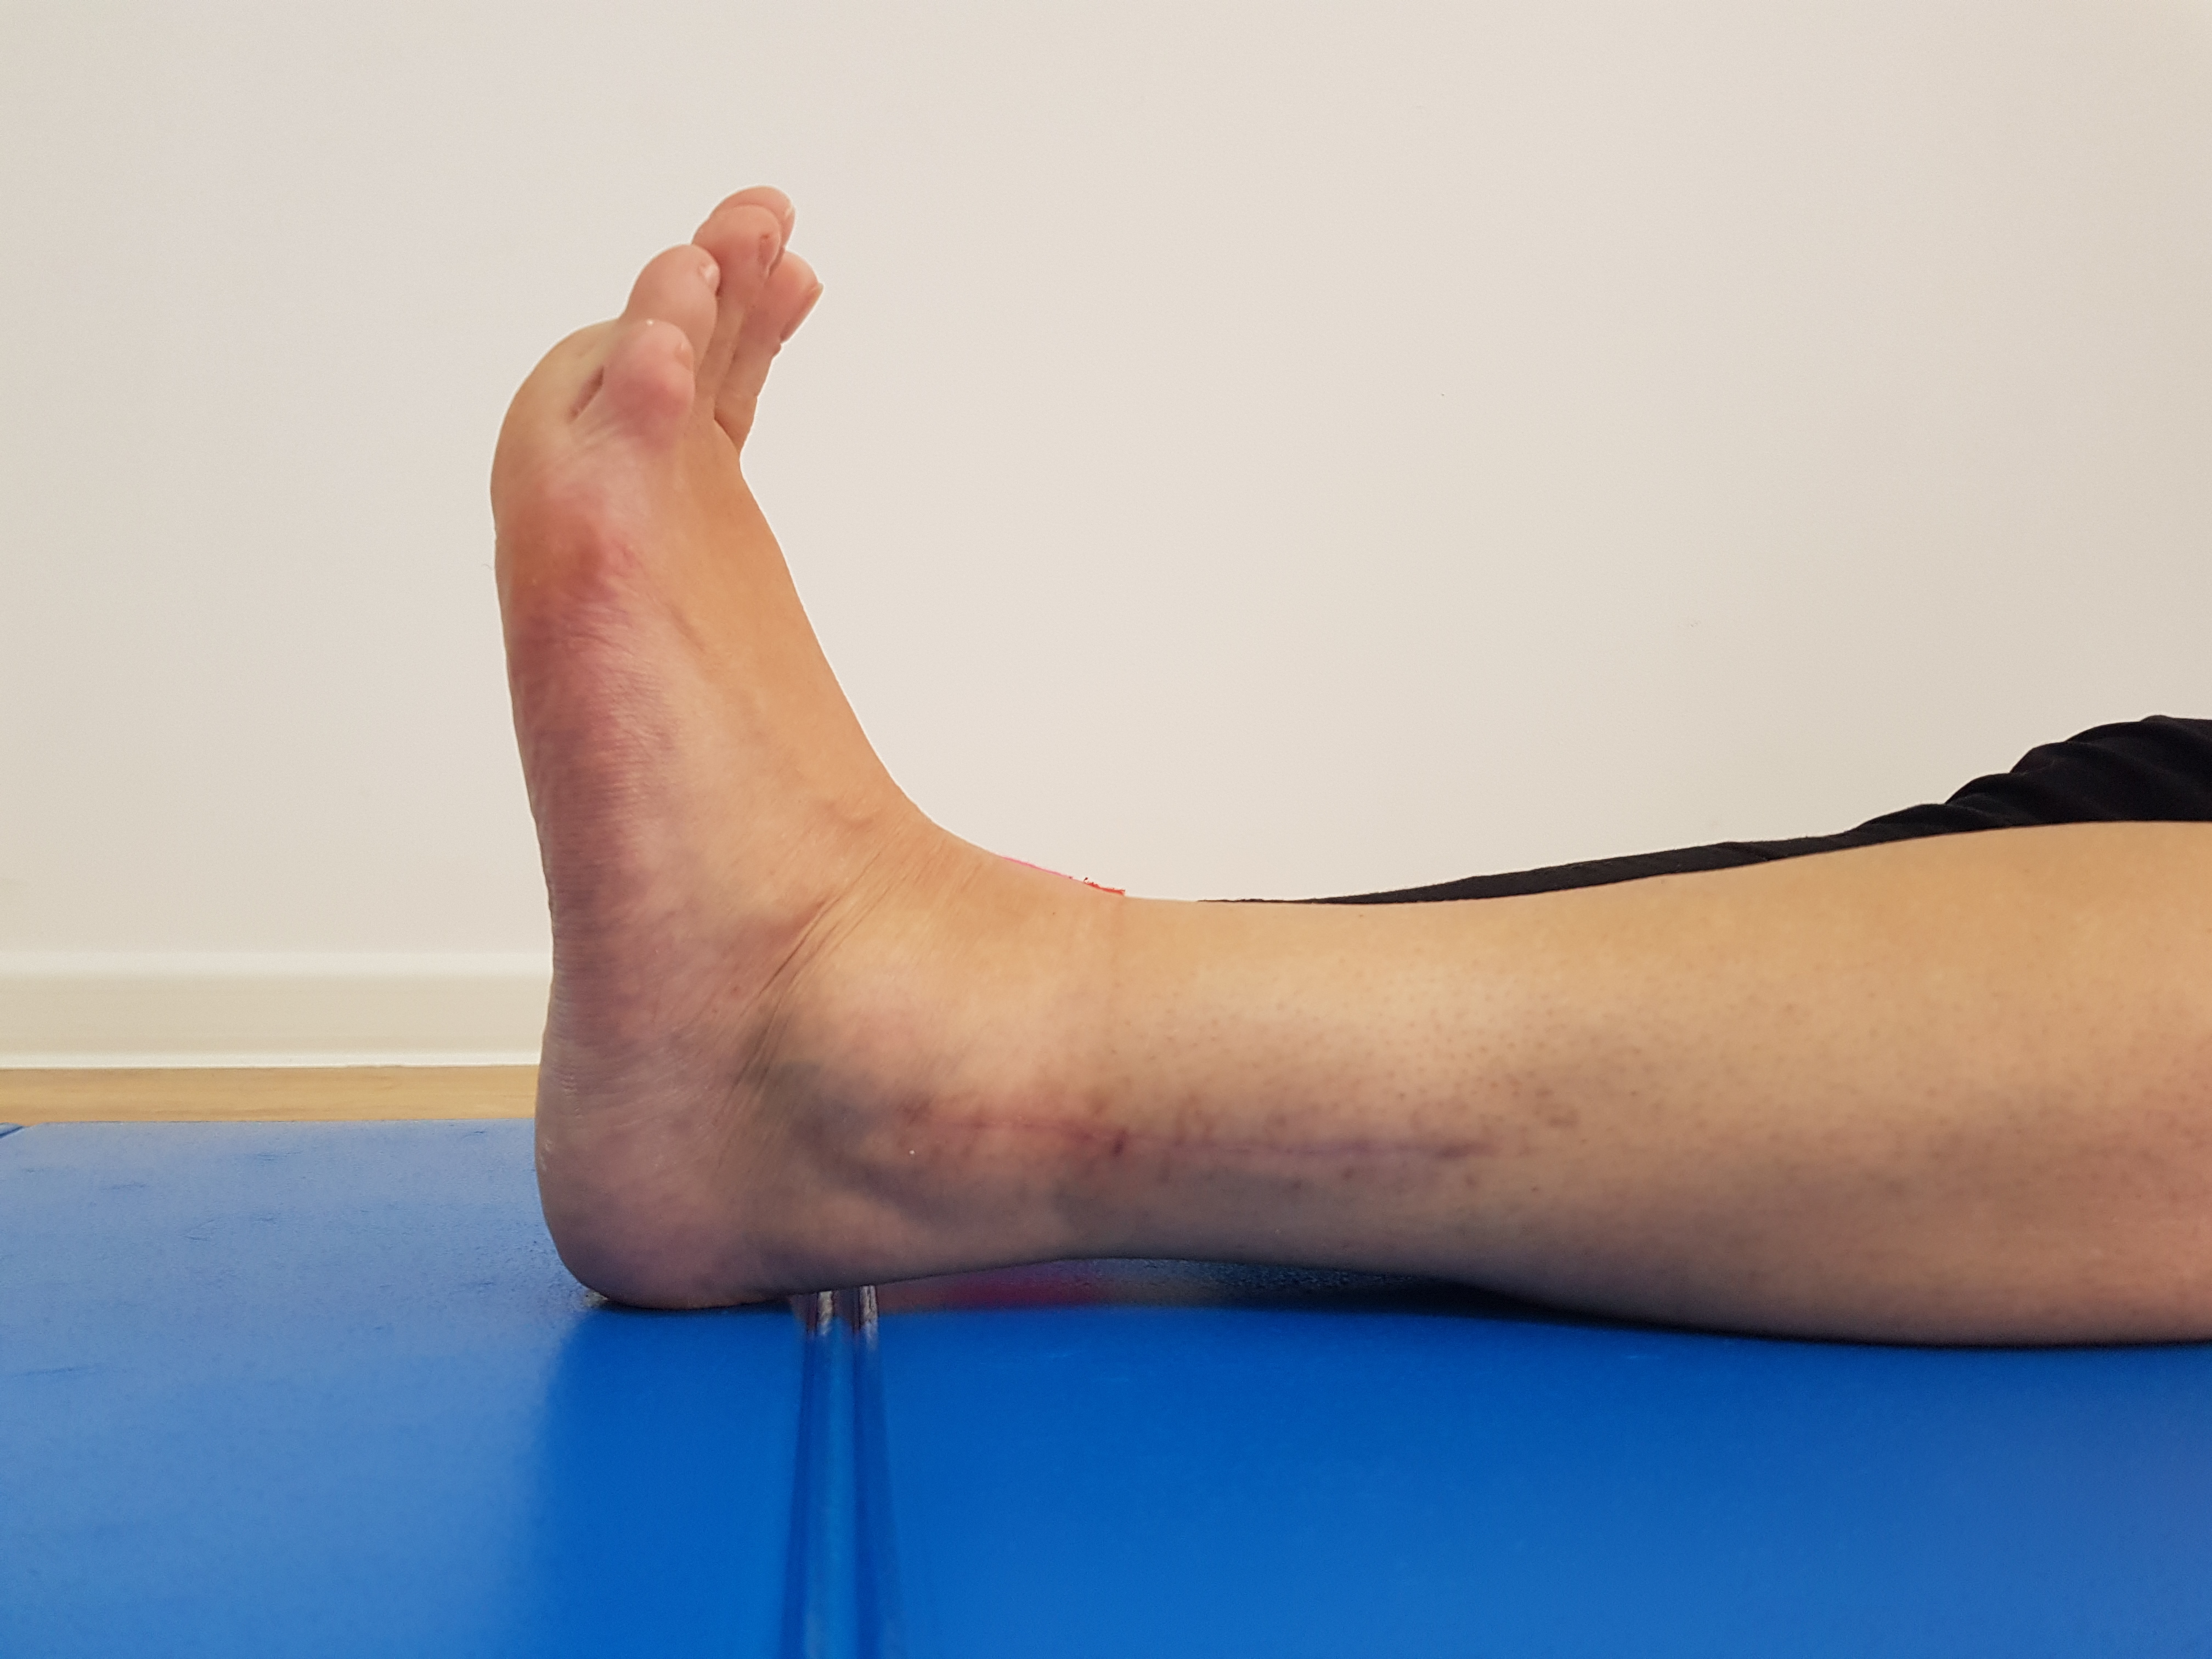

FRACTURA TRIMALEOLARA STANGA